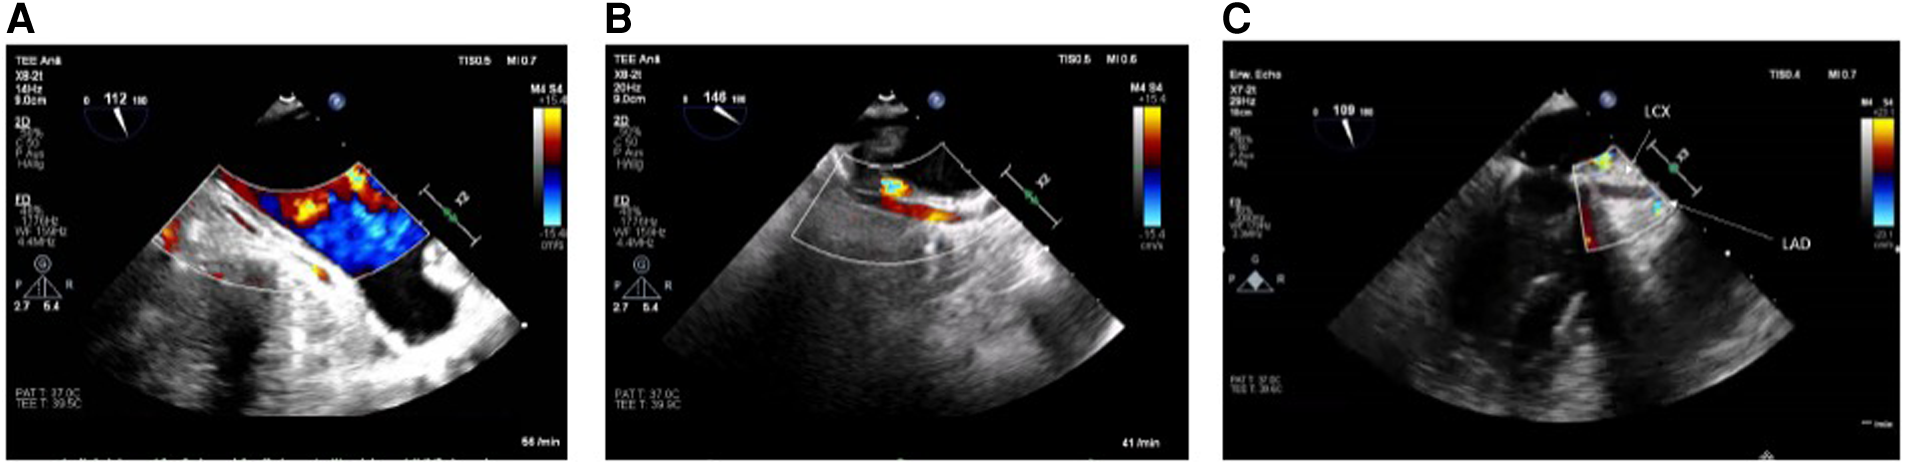

If no flow (in case of circumflex obstruction) or aliasing (in case of circumflex stenosis) can be visualized after mitral valve repair or if there is even an abruption seen of the LCX at best with concordant regional wall motion abnormalities (see Figures 1A–C), the findings should be communicated immediately to the surgical team and the targeted therapeutic approach should be discussed. The important role played by the attentive anesthesiologist is impressively emphasized by Landa et al. in their recently published case report in interpreting the ECG and identifying new-onset regional wall motion abnormalities as early signs of myocardial ischemia (36). Using epicardial ultrasound for vascular flow measurements is another way to detect coronary flow impairment, albeit not widely used in the clinical practice (37–40).

Figure 1

(A) LCX in long axis without flow in the midsegment through suture occlusion (TOE view: modified mid-esophageal aortic valve long axis view according to ender et al. (35) (ME AV LAX) with color flow Doppler, Nyquist limit <30 cm/s). (B) As a contrast: inconspicuous longitudinal view of a prominent LCX (TOE View: modified Mid-esophageal long axis view (mod. ME LAX) with color flow Doppler, Nyquist limit <30 cm/s. (C) Prominent LCX in long axis without flow detection in the proximal third and without the possibility of echocardiography imaging the LCX in the full length due to an estimated occlusion to be expected further peripherally [TOE view: modified mid-esophageal two chamber view (ME 2CH) with color flow Doppler, Nyquist limit <30 cm/s].